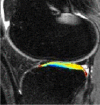

Purpose: To longitudinally evaluate cartilage matrix changes by using magnetic resonance (MR) imaging T1(ρ) (T1 relaxation time in rotating frame) and T2 quantification and to study the relationship between meniscal damage and cartilage degeneration in anterior cruciate ligament (ACL)-reconstructed knees.

Materials and methods: This was an institutional review board-approved, HIPAA-compliant study. Informed consent was obtained. Twelve patients with acute ACL injuries were imaged with 3.0-T MR imaging at baseline (after injury and prior to ACL reconstruction) and 1 year after ACL reconstruction. Ten age-matched healthy subjects were studied as controls. Cartilage T1(ρ) and T2 were quantified in full thickness, superficial, and deep layers of defined subcompartments at baseline and follow-up in ACL-injured knees and were compared with measures acquired in matched regions of control knees. Meniscal lesions were graded by using modified subscores of the Whole-Organ Magnetic Resonance Imaging Score system.

Results: T1(ρ) values of the posterolateral tibial cartilage in ACL-injured knees were significantly elevated at baseline compared with T1(ρ)values of control knees and were not fully recovered at 1-year follow-up. T1(ρ) values of weight-bearing medial femorotibial cartilage in ACL-injured knees were significantly elevated at 1-year follow-up compared with those of control knees. No significant differences in T2 values between ACL-injured and control knees were found. Patients with lesions in the posterior horn of the medial meniscus showed a greater increase of T1(ρ) and T2 from baseline to follow-up in adjacent cartilage than patients without lesions in the medial meniscus.

Conclusion: Quantitative MR imaging T1(ρ) and T2 enable detection of changes in the cartilage matrix of ACL-reconstructed knees as early as 1 year after ACL reconstruction.